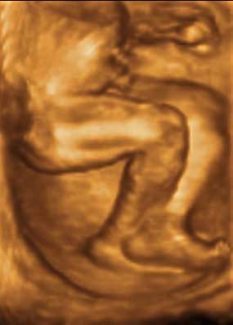

Feto de 26 Semanas